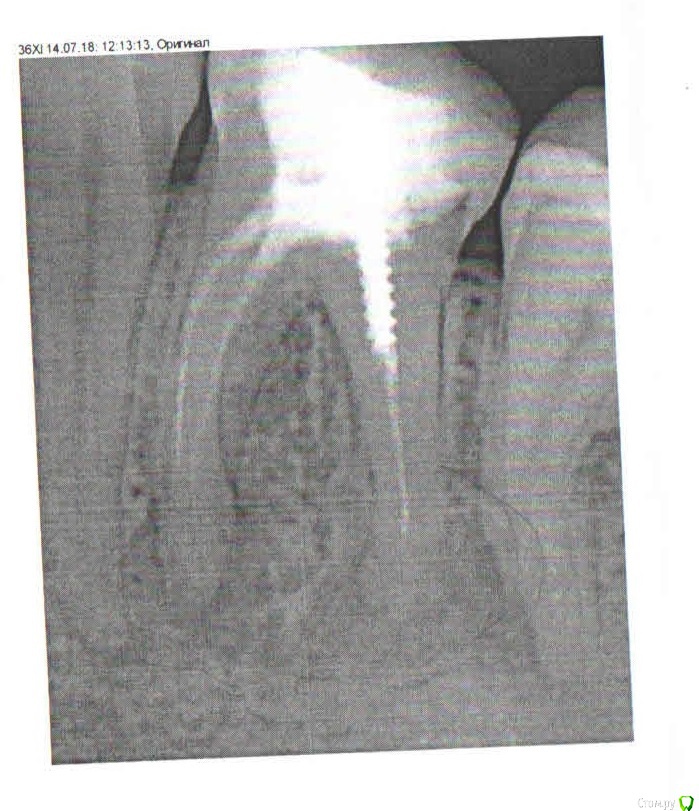

nashe72 Опубликовано 18 ноября, 2018 Автор Поделиться Опубликовано 18 ноября, 2018 Запломбировали корни. Как считаете, нормально сделано ? Ссылка на комментарий